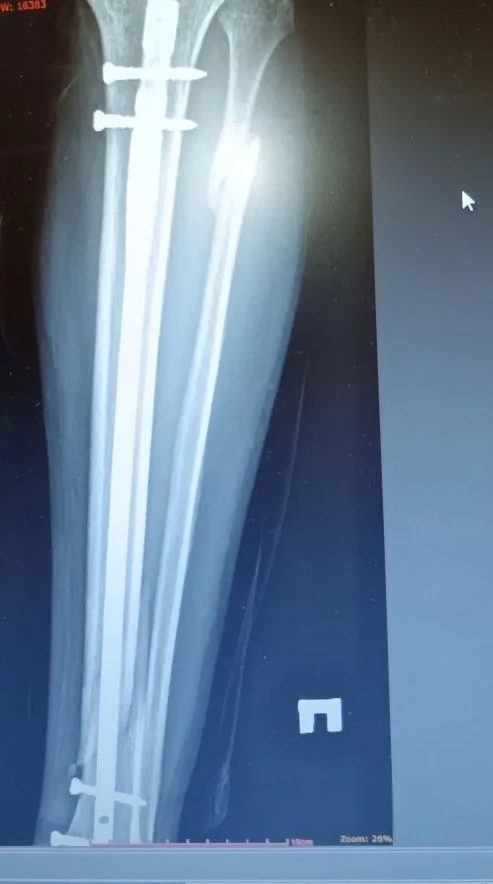

Перелом берцовой кости